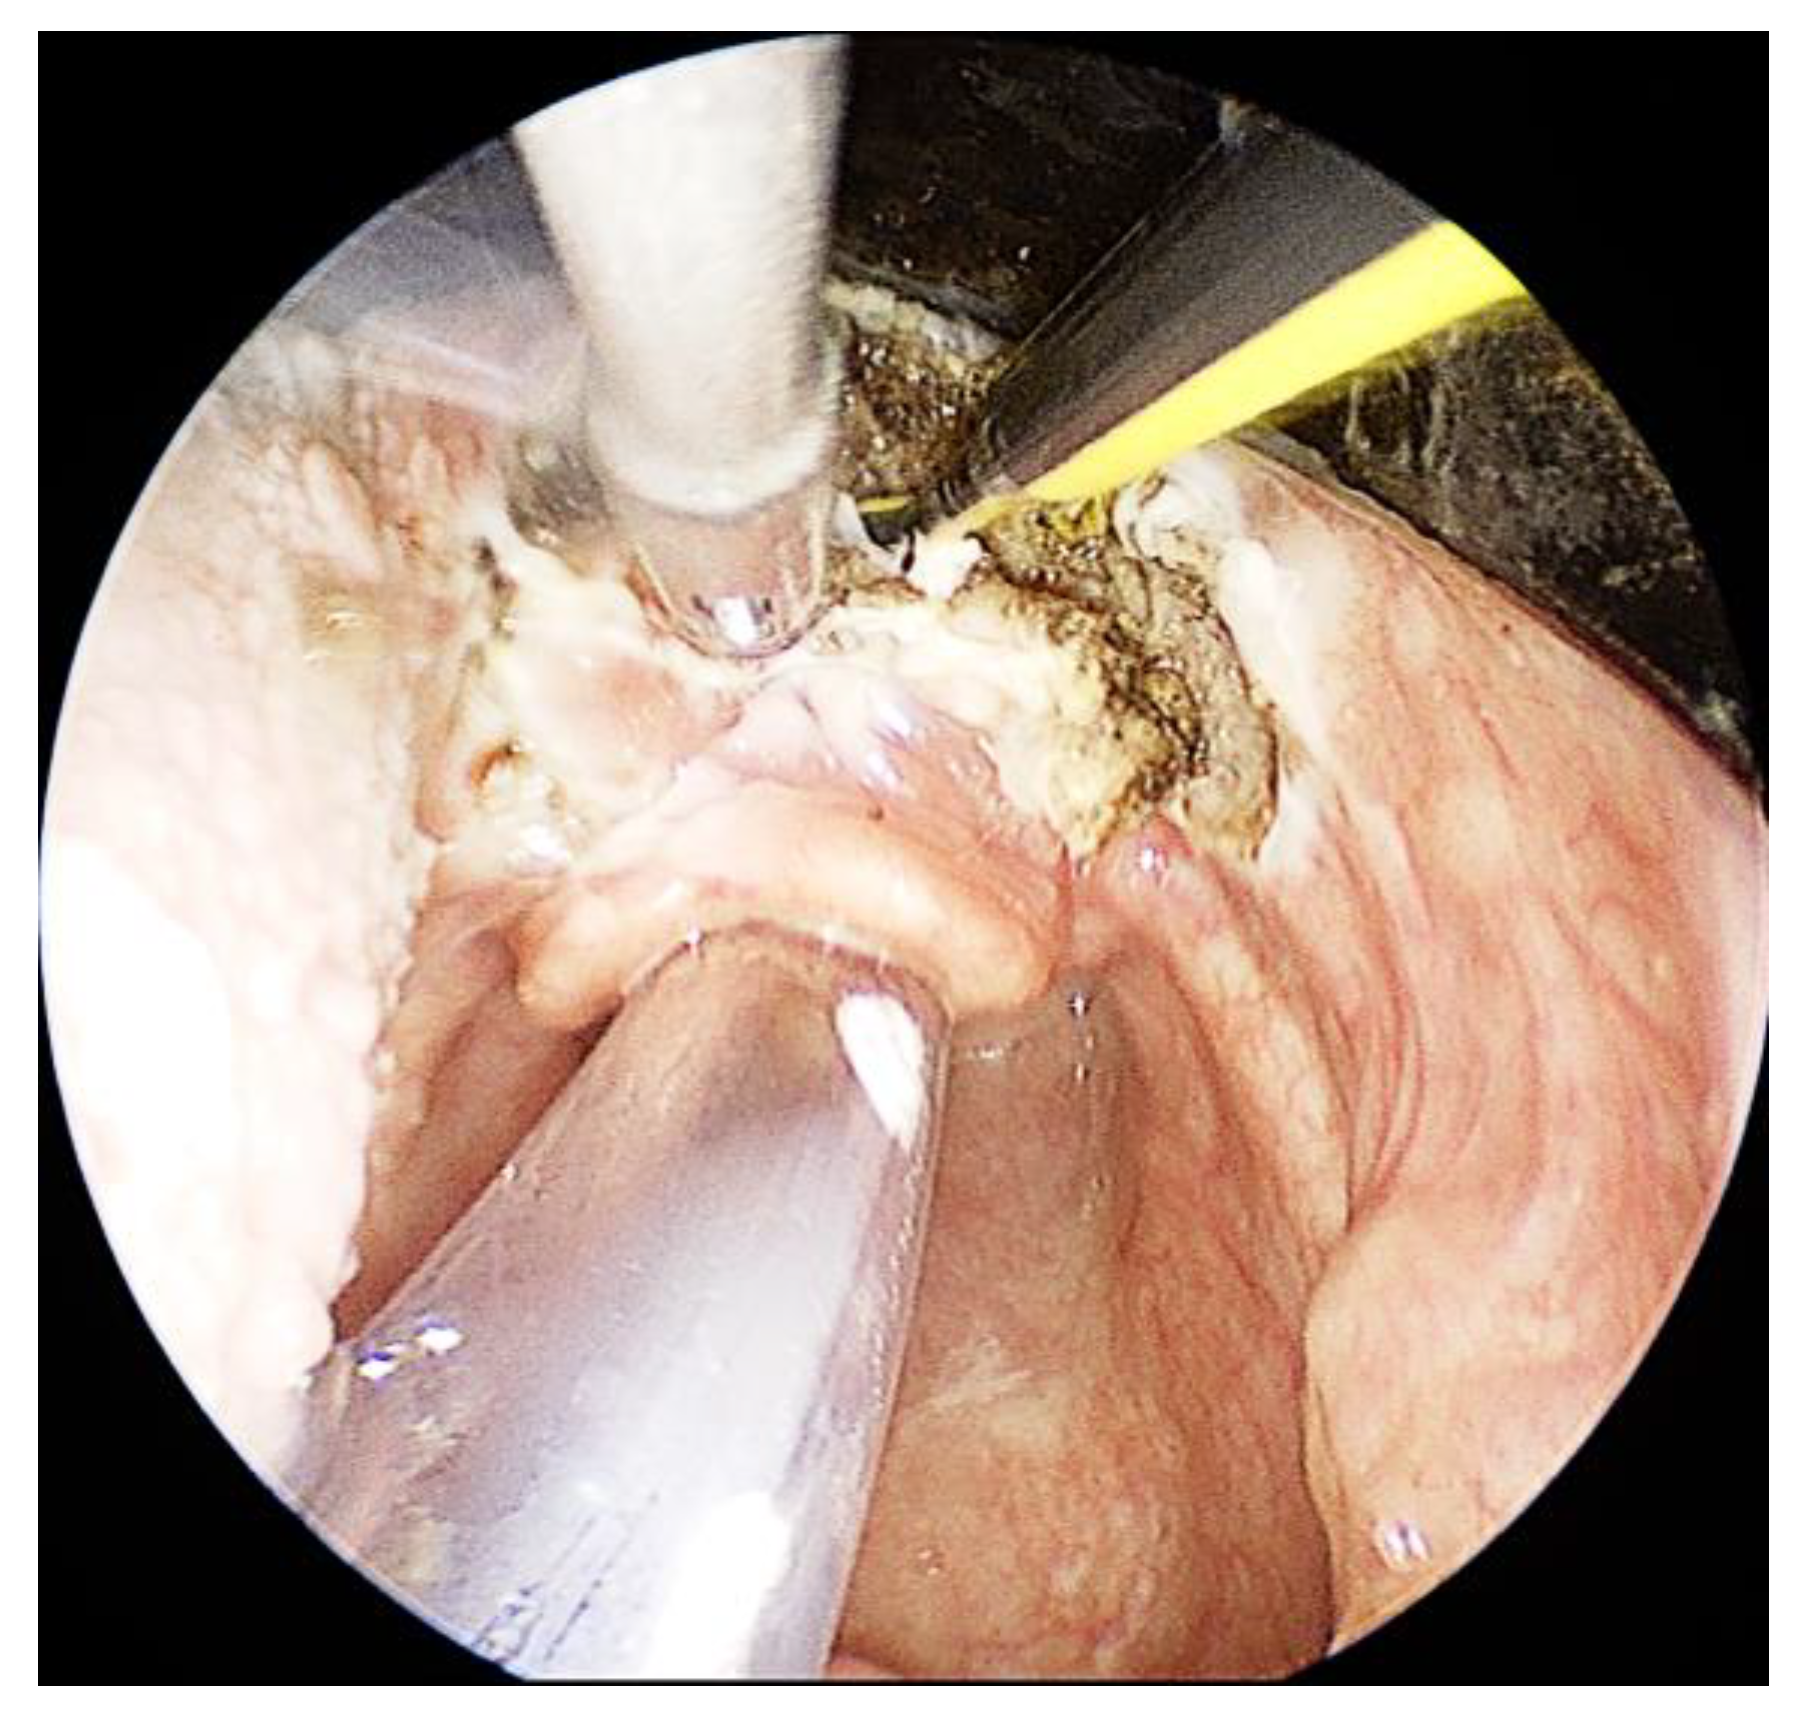

3.1. Case 1